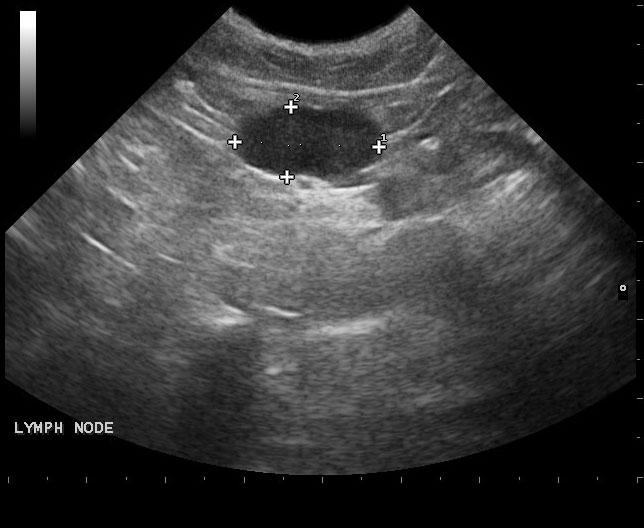

The left kidney was enlarged and measured 5.4 cm with pyelectasia and ill defined fat. Decreased corticomedullary definition was noted with focal capsular expansion at the caudal pole. The right kidney was also moderately to severely enlarged with corticomedullary and pelvic calculi. Loss of corticomedullary detail was noted. Minor subcapsular halo formation was noted with periserosal inflammation. The urinary bladder presented multiple small calculi measuring 0.1-0.3 cm. Mesenteric lymph nodes were enlarged and measured 1.5 cm and 1.8 cm. These lymph nodes were significantly hypoechoic, yet architecture was not distorted at this point. Hyperechoic reactive fat was noted.